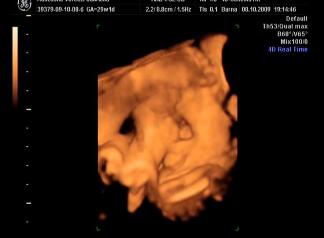

Briell! Nagyon szepek a kepek, a szemtakarosak mindig nagyon cukik, de a labikos sem semmi